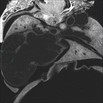

Caption: Serial 2D EFIC image stack in the coronal plane of 904-004-ND reveals dilated ventricular chamber and non-compaction of myocardium in right ventricle

Click thumbnail to play movie. (details)